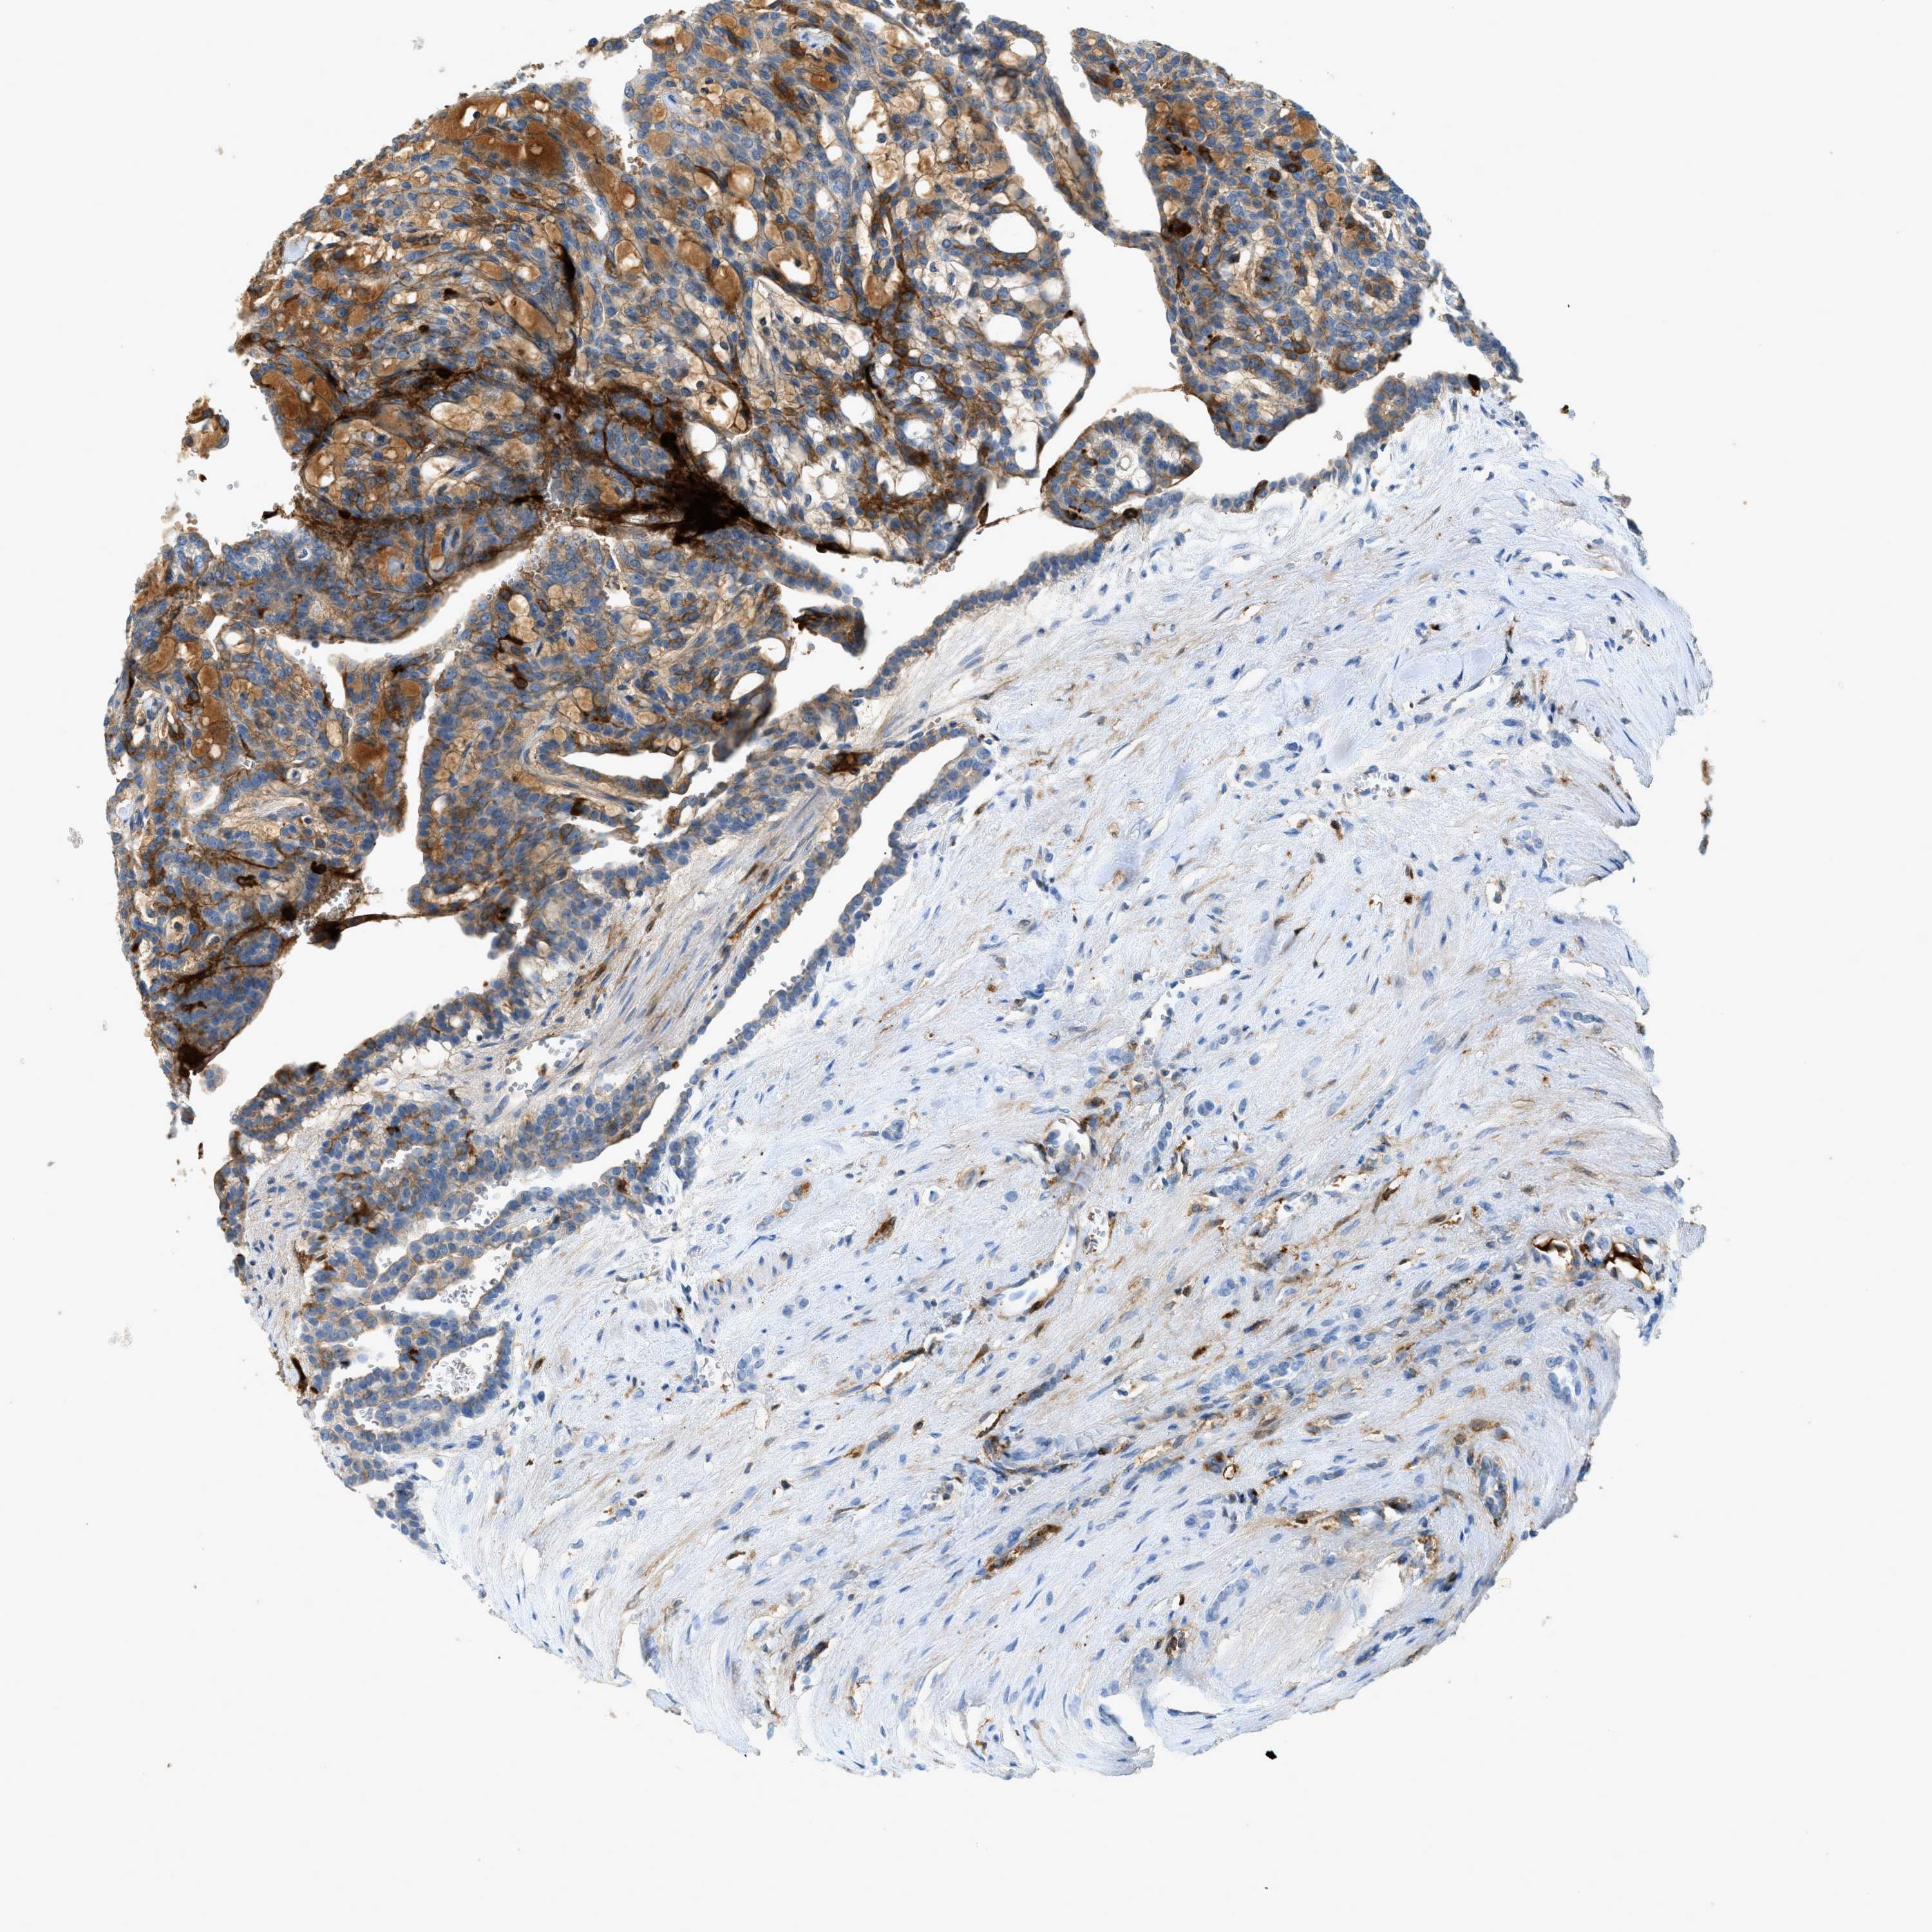

KIDNEY RENAL CLEAR CELL CARCINOMA (VALIDATION) - Interactive survival scatter ploti

F2 is validated prognostic, high expression is unfavorable in Kidney Renal Clear Cell Carcinoma (validation)

: 0.22

Average pTPM 4.4

Number of samples 100